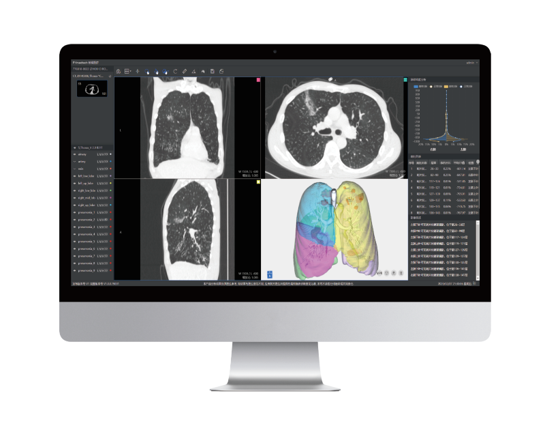

本系統(tǒng)是根據(jù)最新版新型冠狀病毒肺炎影像學(xué)診斷指南推出的針對新型冠狀病毒肺炎的輕量級輔助閱片工具。在公司原有AI輔助篩查系統(tǒng)的基礎(chǔ)上,聯(lián)合武漢協(xié)和醫(yī)院,依據(jù)新型冠狀病毒感染肺炎的影像學(xué)表征對原有AI產(chǎn)品做出升級,能夠快速對新冠肺炎疑似病例進行診斷篩查。目前疫情在短時間內(nèi)出現(xiàn)爆發(fā)式的就診需求,尤其是核心地區(qū),難以實現(xiàn)快速精準(zhǔn)的診斷。本系統(tǒng)能夠應(yīng)對可能出現(xiàn)的大規(guī)模病例篩查,有助于及時發(fā)現(xiàn)潛在病例,加強防控。

針對新冠肺炎的各種典型征象如:磨玻璃影(GGO)、斑片影、實性變化等,在短時間內(nèi)進行快速檢測,大大提高閱片效率,助力當(dāng)前新冠肺炎進行大規(guī)模影像篩查。

依據(jù)最新版新型冠狀病毒肺炎影像學(xué)診斷指南中對CT影像診斷的要求,聯(lián)手武漢協(xié)和醫(yī)院,大量高質(zhì)量的數(shù)據(jù)使柏視能夠提供準(zhǔn)確的處理結(jié)果。利用AI實現(xiàn)影像表征的自動定量化分析,通過病灶形態(tài)特征信息、密度信息等提示肺部病變;并能夠自動計算出疑似概率將病例進行分級分區(qū),方便醫(yī)生逐級篩查。

此次新冠肺炎傳播速度快,病情發(fā)展較為迅速,早期、進展期 、重癥期的影像表現(xiàn)有著明顯區(qū)別。本系統(tǒng)還具備對多次檢查結(jié)果進行對比分析的功能,提高診斷效率。同時,為更加方便的應(yīng)對當(dāng)前客戶需求,系統(tǒng)同時具有根據(jù)醫(yī)院的需求生成符合最新型冠狀病毒肺炎診斷指南的結(jié)構(gòu)化圖文報告的功能。